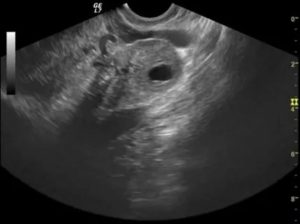

Как проходит диагностика

Врач может определить причину запоздания кровотечения уже на начальном этапе диагностики, во время обычного осмотра. Однако чтобы убедиться в точности поставленного предварительно диагноза дополнительно назначается УЗИ. С помощью ультразвукового исследования выявляется размер опухоли, ее локализация, делается предположение о типе новообразования и способе лечения.